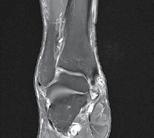

CT-ul cu reconstrucție tridimensională sau RMN genunchi relevă mult mai

bine complexitatea fracturii și dau posibilitatea unui planning preoperator superior estimării radiologice clasice(7). CT-ul este mai rapid și mai ușor de făcut, dar RMN decelează mai bine leziunile de menisc sau ligamentare.

Se practică radiografii standard, examinare CT sau RMN.

Radiografiile se fac în cel puțin 3 incidențe: antero-posterioară, laterală și notch intercondilar.

Incidența antero-posterioară poate decela: o bandă osteoscerotică intensificată, specifică fracturii cu înfundare, separarea unui fragment osos, incongruență articulară femuro-tibială. O înfundare mai mare de 6 mm sau/și o incongruență articulară cu lărgirea acesteia mai mult de 5 mm sunt sugestive pentru leziuni de menisc lateral, ligament colateral lateral sau ligament încrucișat posterior(5). O înfundare sau lărgire articulară mai mare de 8 mm este deseori asociată cu o leziune de menisc medial(6).